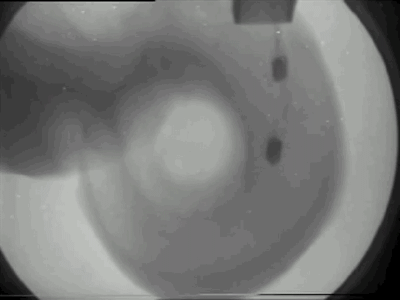

原理:上图是在X光帮助下手术植入人工耳蜗的过程。和负责放大声音的助听器不同,人工耳蜗是一种声-电信号转换器,可以将声音信号转化成电信号,通过植入的电极阵列直接刺激听觉神经从而产生听觉感受。- _, Y) E0 q% K6 M3 `5 V: x

人工耳蜗示意图。图片来自:nidcd.nih.gov5 T8 a% c. I# A1 x4 ?$ i